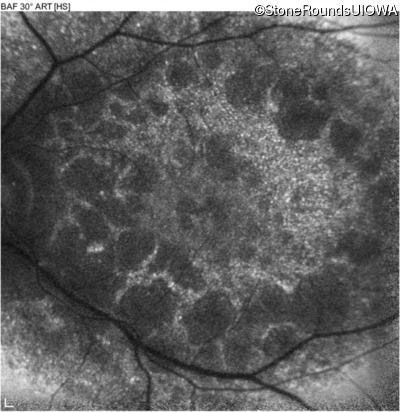

Blue Autofluorescence - Left - 10/400 sc

Exemplar